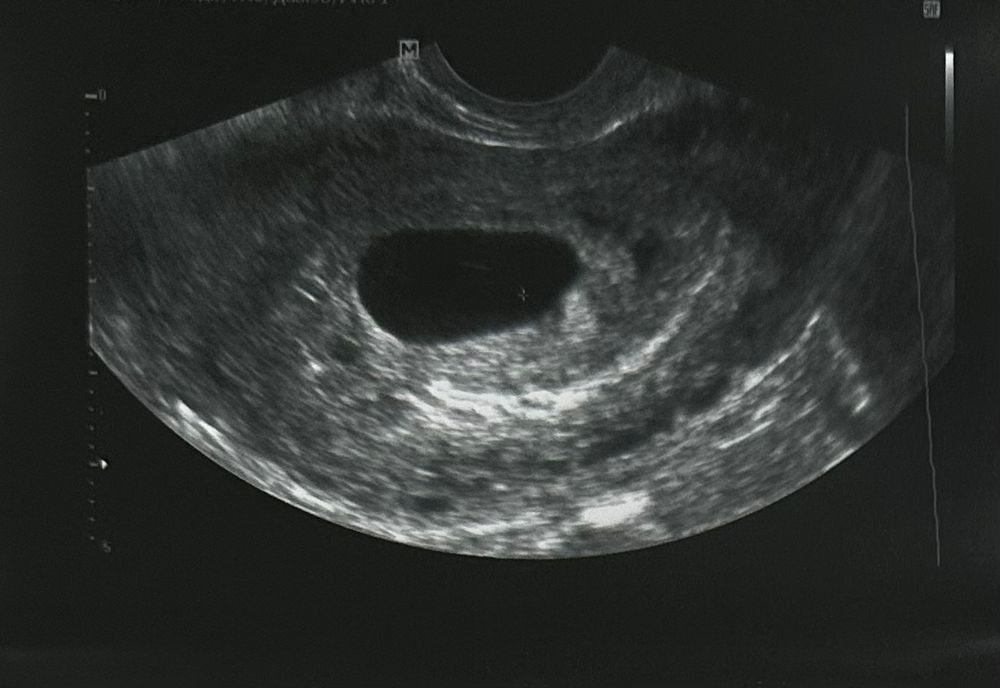

Ну что ж, сходила на УЗИ. Эмбриона нет.

По месячным - 9 акушерская неделя.

20 дней назад ПЯ было по размерам соответствующим сроку 5,3.

Сегодня ПЯ по размерам на 6,4 недели.

ЖМ нет, эмбриона нет